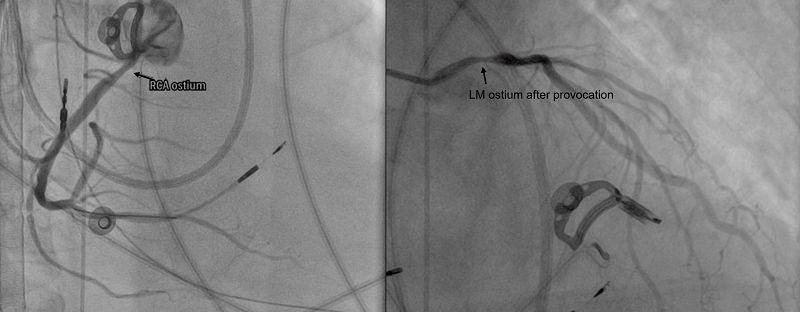

心臟功能室葉冠宏主任隨即仔細檢視心電圖動態變化,並考量半年內多次心跳停止的病史,安排心導管誘發測試,最終抽絲剝繭確診為罕見且嚴重的「雙側冠狀動脈痙攣」,造成冠脈劇烈收縮、血流瞬間減少甚至中斷,進而誘發致命心律不整與心跳停止。在給予抗痙攣藥物治療後,洪先生一度轉危為安並成功移除葉克膜,未料住院期間仍再度發生心跳停止,需再次即時搶救與二度葉克膜緊急裝機。

葉冠宏主任指出,常見的冠狀動脈疾病包括動脈硬化與血管阻塞,而「冠狀動脈痙攣」則是血管抽筋,為血管突然且劇烈收縮,使血流瞬間減少甚至中斷,可能引發嚴重心律不整,甚至導致心跳停止。臨床觀察顯示,冠狀動脈痙攣多與多重因素相關,包括高血壓、高血脂、糖尿病等三高族群風險較高,同時也與自律神經失衡有關,特別是交感神經過度活化,容易造成血管異常收縮。他進一步說明,部分病人在發作前可能出現胸悶、胸痛、心悸或冒冷汗等症狀,也有病人如洪先生ㄧ般,一旦發作馬上併發嚴重心律不整直接導致猝死。因此臨床上需透過病史、心電圖變化、冠狀動脈攝影或心導管進行誘發測試等檢查綜合判斷,及早發現並介入治療,才能降低致命風險。